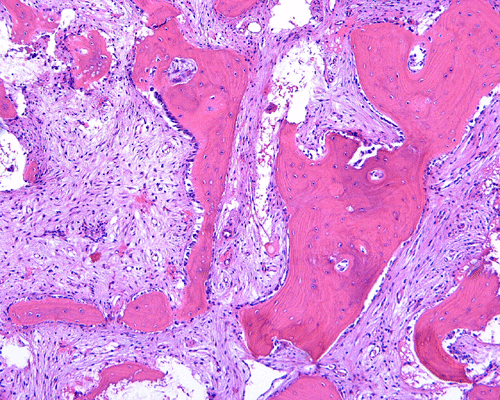

Pathology of the case: The specimen consists of multiple small pieces of irregular tissue fragments obtained by curretage. Histologically, the lesion tumor consists of bland spindled cells embedded in a collagenous matrix and arranged in a storiform pattern with frequent hemorrhage (Panel B). Entrapped residual bone associated with foci of osteoclastic type giant cells are present (Panel C). A scant number of epithelial islands are also scattered within this spindle cell background (Panel D, E, and F). On high magnification, no significant nuclear atypia or pleomorphism is noted in either the spindle cell or epithelial cell components. In other parts of the specimen, the spindle cell tumor is admixed with spiculated fragments of woven bone rimmed by osteoblasts (Panel H, I, and J). Small islandsIt of epithelial cells are also noted in these areas (Arrow in Panel H).

Differentiated (osteofibrous dysplasia-like) adamantinomas are exclusively intracortical. The microscopic appearance of differentiated adamantinoma resembles osteofibrous dysplasia. Spindled cells with a storiform pattern mingle with fragments of bone. The bony fragments are typically rimmed by osteoblasts and exhibit gradual progression from woven to lamellar bone as one moves from the center to the periphery of the lesion. Epithelial islands can be seen interspersed focally within the aforementioned osteofibrous dysplasia-like stroma. The epithelial component is much less prominent than in the classic variety of adamantinoma. Immunohistochemistry for cytokeratin is a very useful adjunct to demonstrate these scattered epithelial elements and they can be very small and subtle as demonstrated in this case.